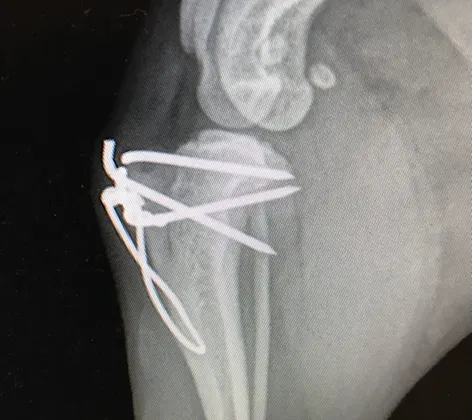

TPLO Surgery

Clinical signs of CrCL tear in dogs range from intermittent limping to acute complete non-weight bearing lameness in the hind limb. CrCL tears can be partial, complete, or complete with a damaged meniscus.

Cruciate Ligament Repair

Cruciate ligament disease: Cruciate ligament rupture aka ACL injury or Torn ACL in dogs is by far the most common orthopedic injury we experience in our practice.

Patellar Luxation

Patellar luxation (dislocating kneecap) occurs when the knee cap dislocates and is both painful and a cause of chronic lameness and arthritis.